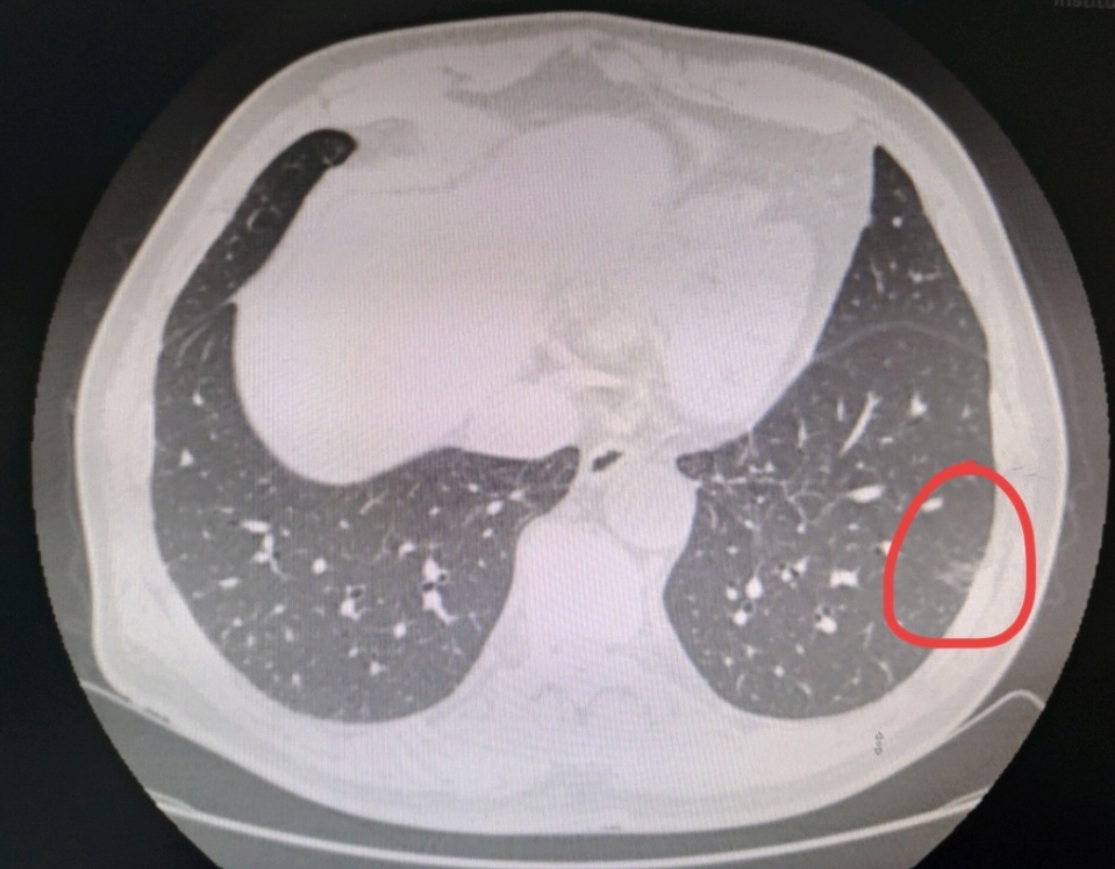

肺磨玻璃结节是肺癌吗

1、肺磨玻璃结节不能仅凭认定就断定是癌虽然肺磨玻璃结节与肺癌之间存在一定的关联,但并非所有肺磨玻璃结节都是恶性的肺磨玻璃结节是指在肺部CT检查中,表现为密度轻度增高的云雾状淡薄影圆形结节,样子像磨砂玻璃一样,所以叫磨...